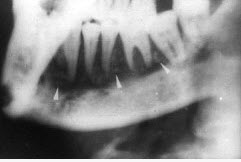

女,32岁,右下后牙龈向外膨隆,后牙渐松动3个月。X线片(如图)示右下颌磨牙区颌骨呈蜂房样改变,病变区牙根呈锯齿状吸收。该病人最可能的诊断是()。

A.右下颌骨角化囊肿

B.右下颌骨骨巨细胞瘤

C.右下颌骨骨肉瘤

D.右下颌骨成釉细胞瘤

E.右下颌骨中央性颌骨癌